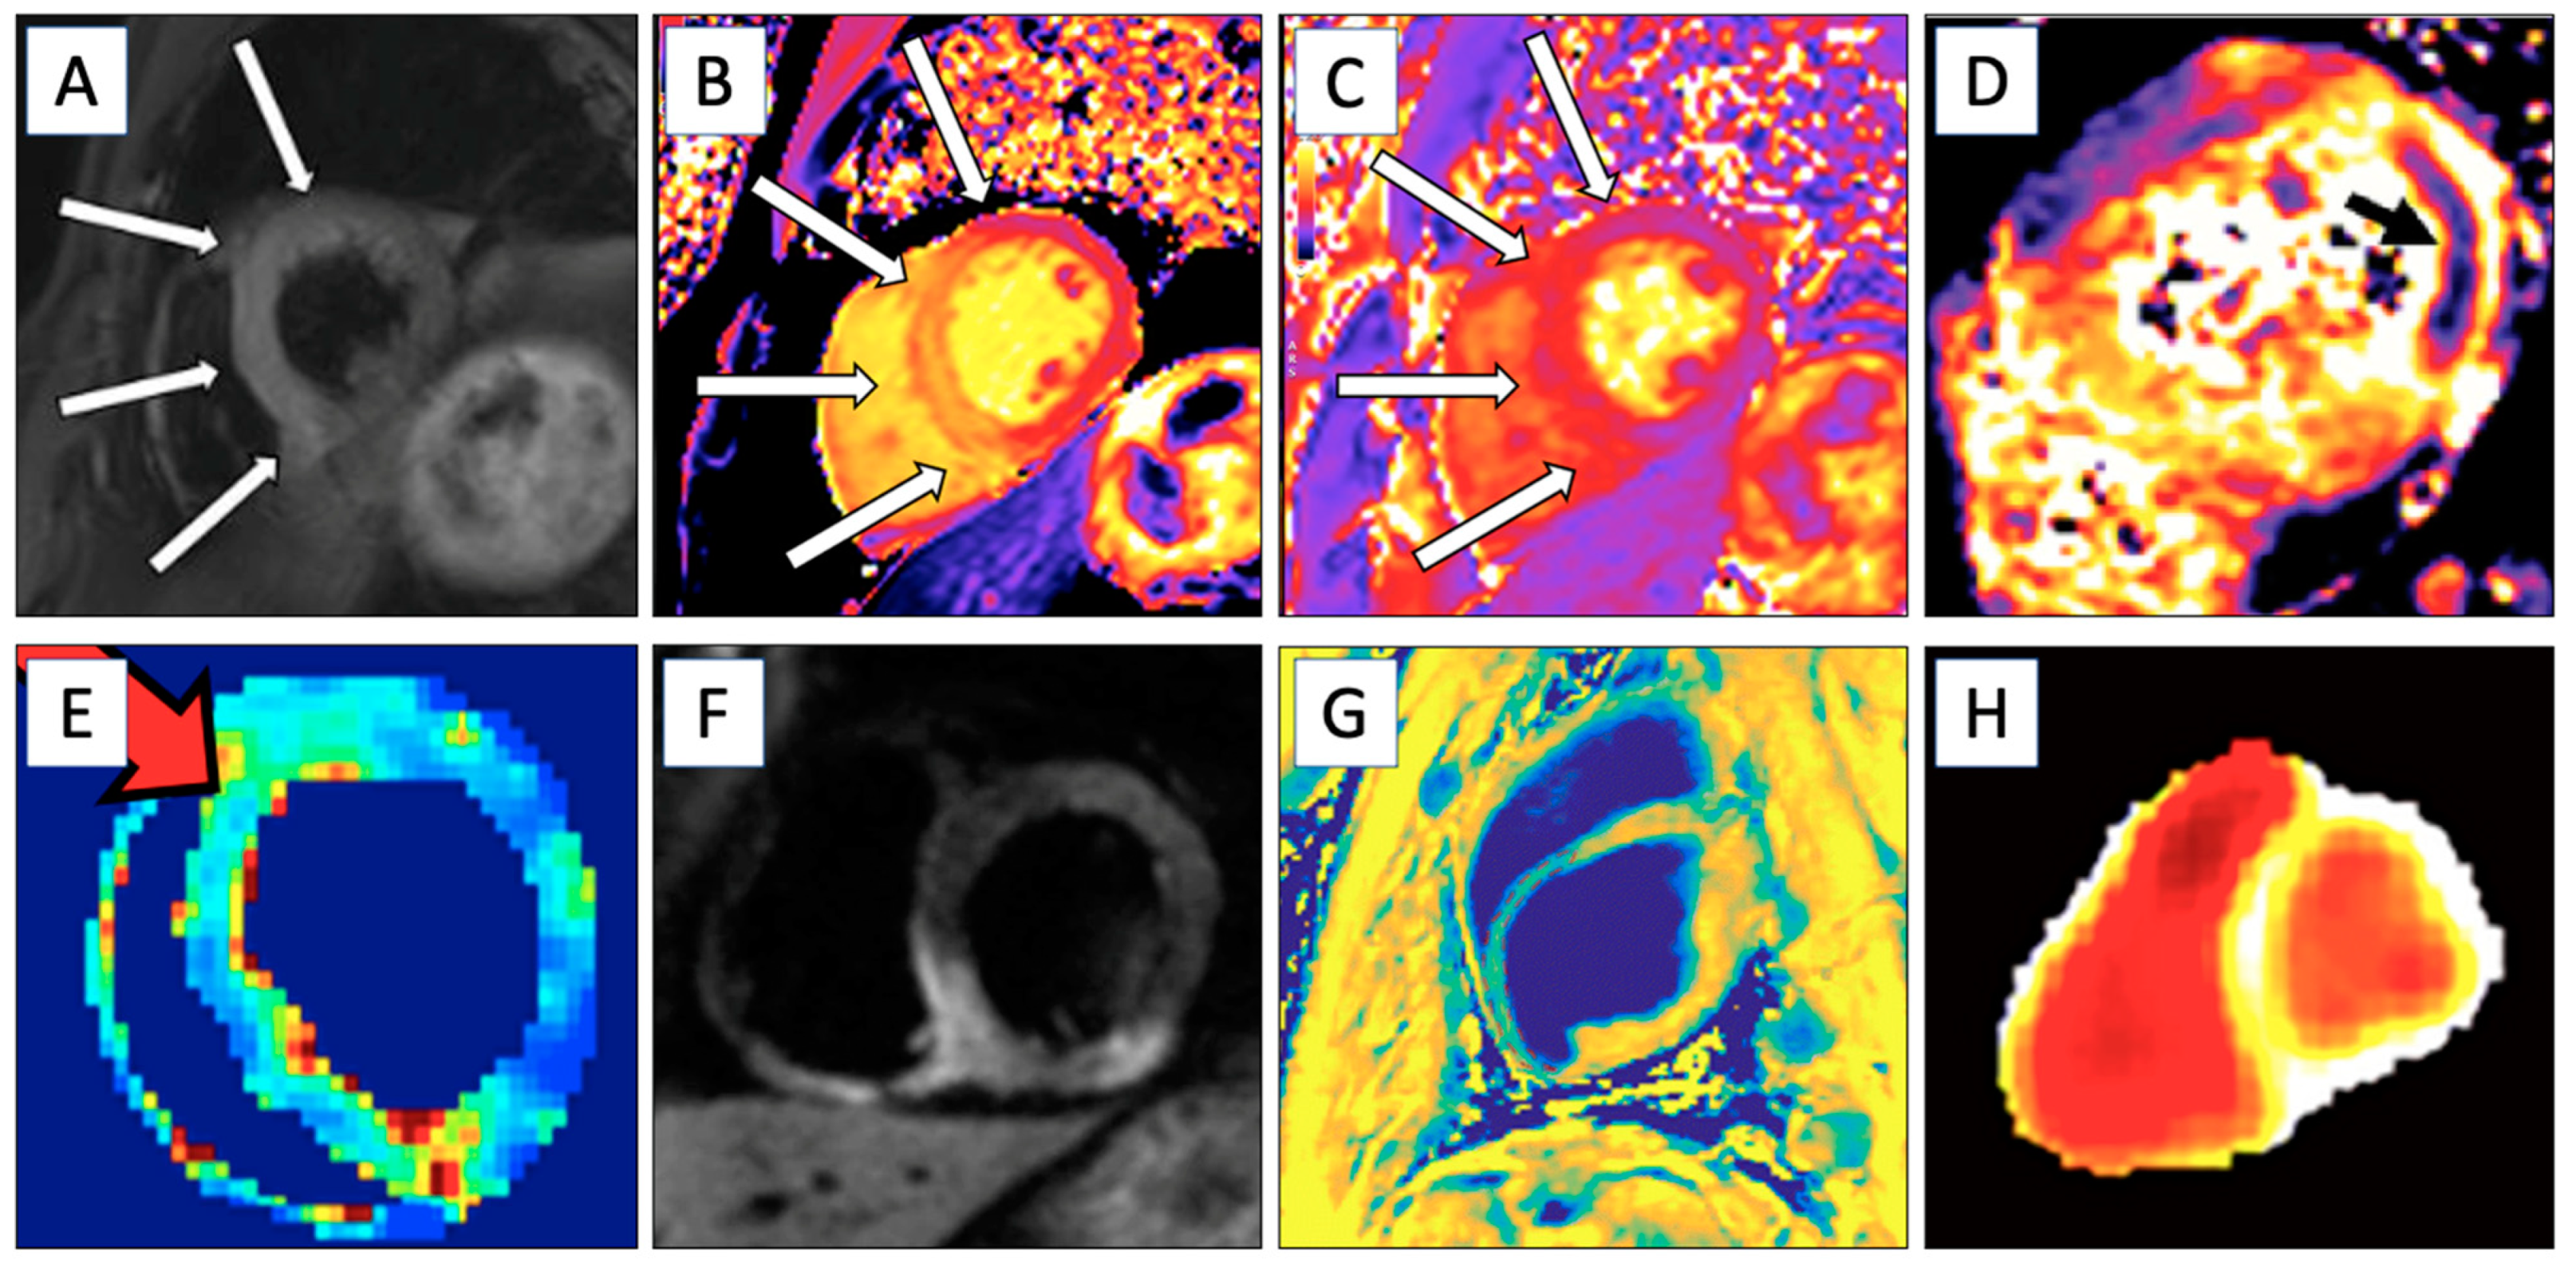

| CMR Technique | Information Obtained | LGE | Examples of Diseases Studied | Figure |

|---|---|---|---|---|

| T1 Mapping | Identifies myocardial tissue properties like fibrosis. Extracellular volume can be measured if LGE is used. | No/Yes | Myocardial infarction, myocarditis, amyloidosis, etc. | Figure 2B |

| T2 Mapping | Evaluates edema, suitable for detection of acute ischemic areas. | No | Acute ischemia, myocarditis, etc. | Figure 2C and Figure 3 |

| T2* Relaxation | Myocardial hemorrhage in the acute phase. | No | Ischemic hemorrhage and iron overload | Figure 2D |

| Late Gadolinium Enhancement | Determines ischemic and scar areas and visualizes damage from healthy myocardial tissue. Perfusion imaging. | Yes | Ischemic heart disease (fibrosis), inflammation, etc. | Figure 2A and Figure 3 |

| T1ρ Imaging | Detects subtle changes in tissue composition, with enhanced contrast and sensitivity for ischemia and scarring. | No | Fibrosis | Figure 2E |

| RAFFn Imaging | Analyzes molecular levels of ischemic and scar tissue with low SAR values, suitable for fibrotic areas. | No | Fibrosis | Figure 3 |

| Magnetization Transfer Imaging | Determines water–macromolecular proton interactions and enhances contrast between myocardial infarction and remote myocardium. | No | Myocardial infarction | Figure 2F |

| Diffusion-Weighted Imaging | Detects areas of myocardial infarction by identifying regions with restricted water diffusion, which correspond to ischemic injury. Also detects myocardial fibrosis with altered diffusion properties. | No | Ischemic heart disease | Figure 2G |

| Hyperpolarized MRI (hMRI) | Determines real-time cardiac energy metabolism with hyperpolarized [1-13C]pyruvate. | No | Ischemic heart disease | Figure 2H |